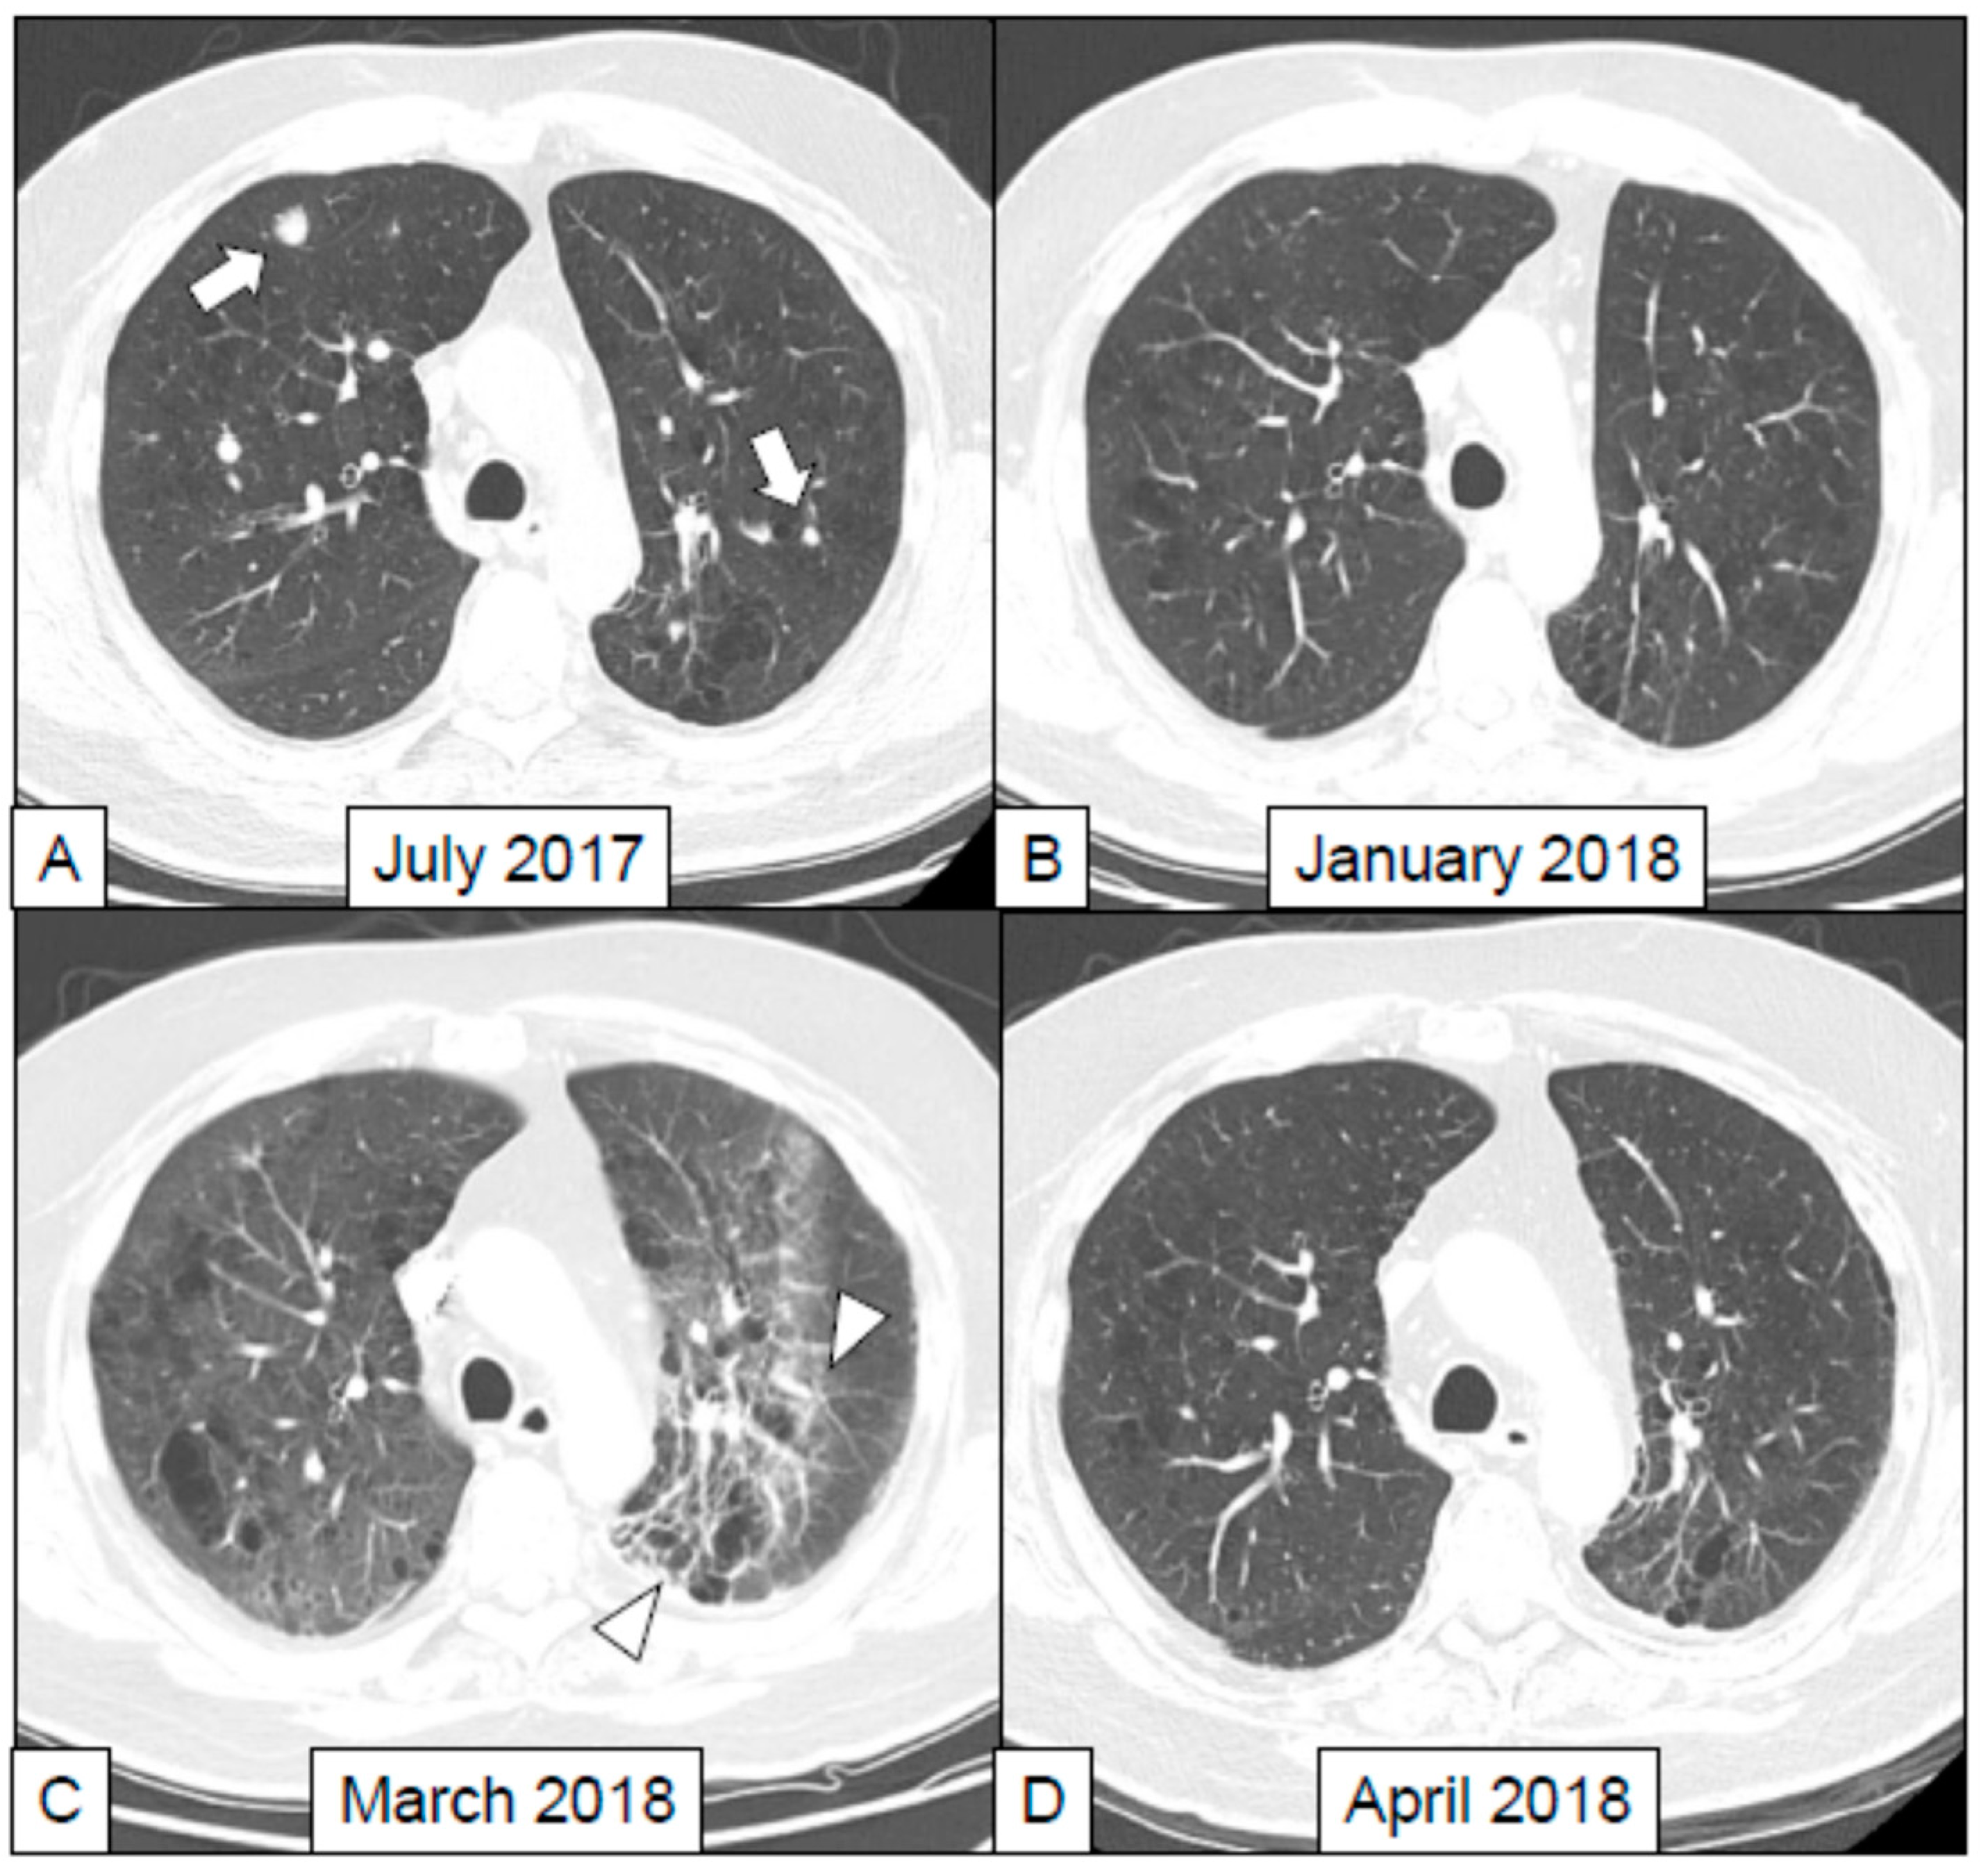

- Nishino, M.; Ramaiya, N.H.; Awad, M.M.; Sholl, L.M.; Maattala, J.A.; Taibi, M.; Hatabu, H.; Ott, P.A.; Armand, P.F.; Hodi, F.S. PD-1 Inhibitor-Related Pneumonitis in Advanced Cancer Patients: Radiographic Patterns and Clinical Course. Clin. Cancer Res. 2016, 22, 6051–6060. [Google Scholar] [CrossRef] [PubMed]